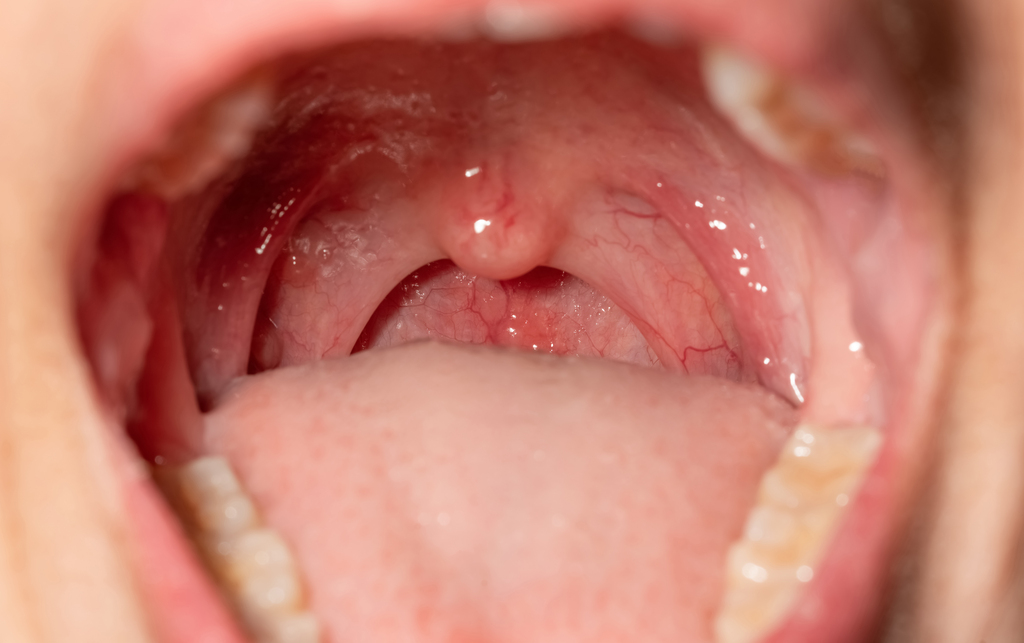

Hal ini dapat terjadi jika anak yang terinfeksi Streptokokus beta-hemolitikus grup A (GAS) tidak segera ditangani. Menurut Dr. Rizky, sakit tenggorokan yang disebabkan oleh infeksi GAS dapat berkembang menjadi demam rematik, suatu reaksi sistem kekebalan tubuh yang terjadi 1-5 minggu setelah infeksi awal. Demam rematik ini kemudian dapat menyebabkan komplikasi serius, termasuk masalah jantung.

Itulah yang kita sebut penyakit jantung rematik," lanjutnya, seraya menambahkan bahwa kondisi ini dapat memicu gagal jantung dan stroke, sehingga memerlukan tindakan operasi. Tanda dan gejala demam rematik biasanya muncul 1-5 minggu setelah sakit tenggorokan akibat SGA. Gejalanya dapat berupa nyeri dan pembengkakan pada sendi yang terkena, gelisah, dan ruam merah melingkar.